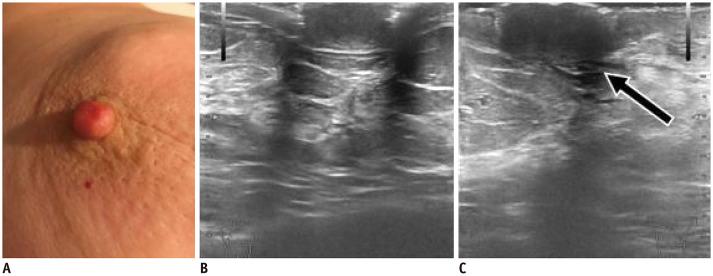

Ultrasound (US) is an attractive diagnostic approach to identify both common and uncommon nipple pathologies, such as duct ectasia, nipple abscess, nipple leiomyoma, nipple adenoma, fibroepithelial polyp, ductal carcinoma (restricted to nipple), invasive carcinoma, and Paget's disease. US is the reliable first-line imaging technique to assess nipple pathologies. It is useful to identify and characterize nipple lesions. Additionally, we have presented the mammography and MRI outcomes correlated with histopathologic features for the relevant cases.